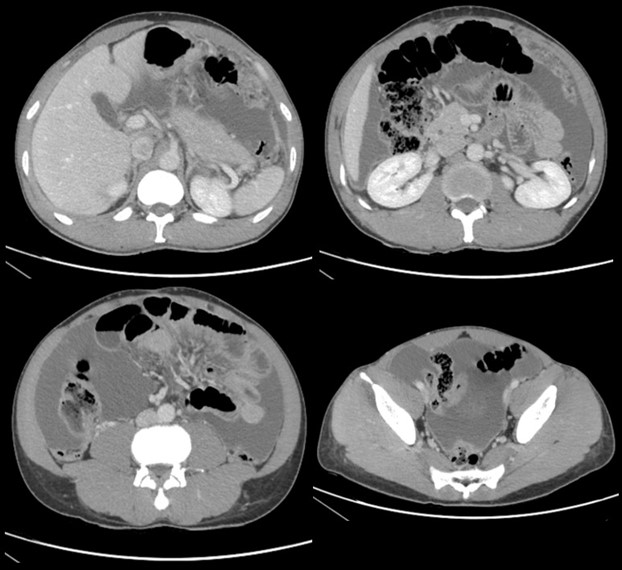

Hallazgos ecográficos

Ascitis a estudio, sugestiva de peritonitis tuberculosa

Se completa el estudio en hospitalización con serología de virus hepatotropos, positiva para VHB, adenosina desaminasa (ADA) 127.10 U/l, interferón gamma 1433 pg/ml, detección de interferón gamma (IGRA) positivo, marcadores tumorales negativos y cultivos de líquido ascítico inicialmente negativos, en los que tras larga incubación se aísla Mycobacterium tuberculosis complex confirmando el diagnóstico de presunción de peritonitis de etiología tuberculosa.

La ecografía clínica es una herramienta esencial en el diagnóstico de la ascitis. Permite la identificación y cuantificación precisa del líquido, además de evaluar su distribución. La realización de paracentesis guiada por ecografía es fundamental para establecer la causa subyacente de la ascitis, permitiendo obtener muestras de líquido para su análisis. La combinación de la ecografía y la paracentesis mejora la precisión diagnóstica y guía la atención médica apropiada.